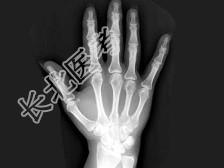

- 单项选择题女,41岁, 纺织工,腕部疼痛无力数周, 结合CR和MR,最可能的诊断是 ( )

B、月骨缺血坏死